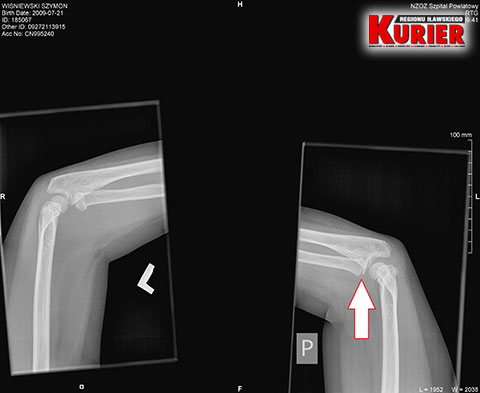

– Tu pan doktor, w odróżnieniu do lekarki w Iławie, zlecił wykonanie prześwietlenia jednej i drugiej ręki, dla porównania – opowiadała nam pani Karolina. – Gdy tylko zobaczył zdjęcie, od razu stwierdził złamanie łokcia z przemieszczeniem. Nie było już pytania, czy dziecko chce mieć założoną szynę czy nie. Od razu to zrobiono i skierowano nas do Olsztyna.

– Pytałam tam doktora, czy na zdjęciu z prześwietlenia w Iławie widać złamanie – mówiła w rozmowie z nami kobieta. – Oczywiście potwierdził i pokazał mi nawet, gdzie dokładnie do niego doszło. Konieczna była prawie godzinna operacja, podczas której ustabilizowano rękę drutem. Przeprowadzono ją od razu, bo lekarz mówił, że każda minuta w tym stanie jest na niekorzyść dziecka.

W nowomiejskim szpitalu od razu rozpoznano

złamanie łokcia z przemieszczeniem

W olsztyńskim szpitalu podczas operacji

ustabilizowano rękę chłopca drutem

W nowomiejskim szpitalu dla porównania

wykonano prześwietlenie obu rąk i stwierdzono

w lewej złamanie łokcia z przemieszczeniem